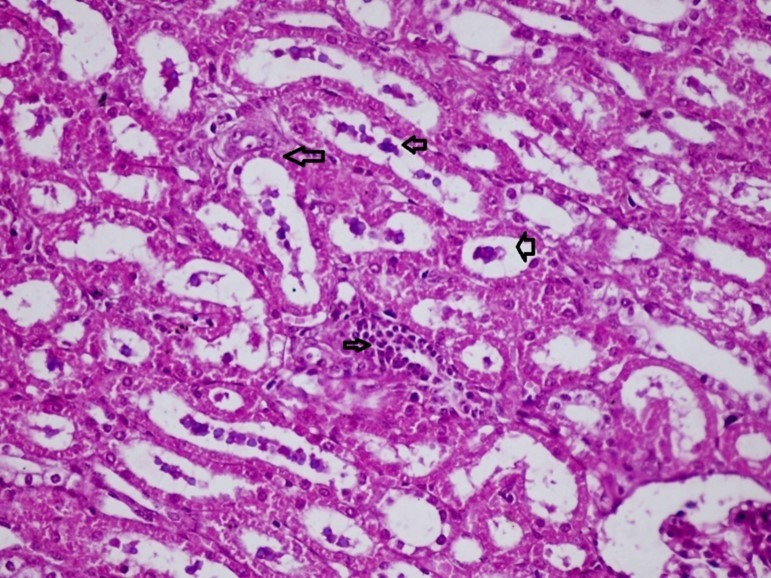

Figures 6.kidneys (dead cattle less than 1 year old) showed severe hydropic degeneration of renal tubular epithelium accompanied by dilated renal tubules, vesicles formations and casts (arrows). (H&E, X 100)

kidneys (dead cattle less than 1 year old) showed severe hydropic degeneration of renal tubular epithelium accompanied by dilated renal tubules, vesicles formations and casts (arrows). (H&E, X 100)

Figures 7.kidneys (dead cattle less than 1 year old) showed severe hydropic degeneration of renal tubular epithelium accompanied by dilated renal tubules, vesicles formations and casts (arrows). (H&E, X 60)

kidneys (dead cattle less than 1 year old) showed severe hydropic degeneration of renal tubular epithelium accompanied by dilated renal tubules, vesicles formations and casts (arrows). (H&E, X 60)